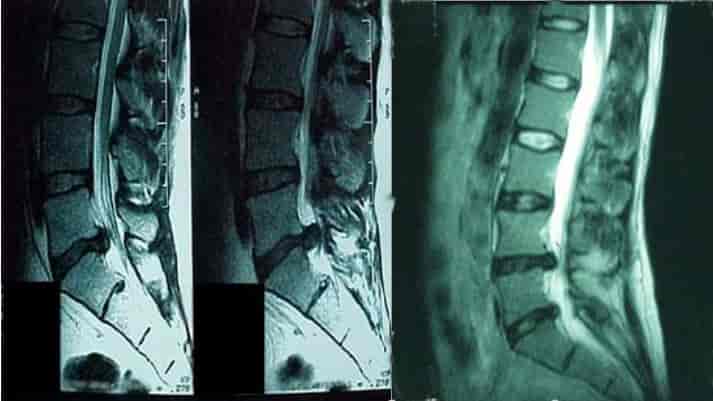

• آزمایش‌ها و تست‌های تشخیصی: معمولاً پزشک با عکس‌برداری به کمک اشعه ایکس شروع می‌کند که به وسیله آن می‌تواند وجود بیماری‌های دیگر مانند تومور یا عفونت را رد کند. سی تی اسکن و ام آر آی برای تصویربرداری جزئی‌تر از عارضه‌های ستون فقرات نیز انجام می‌شود.